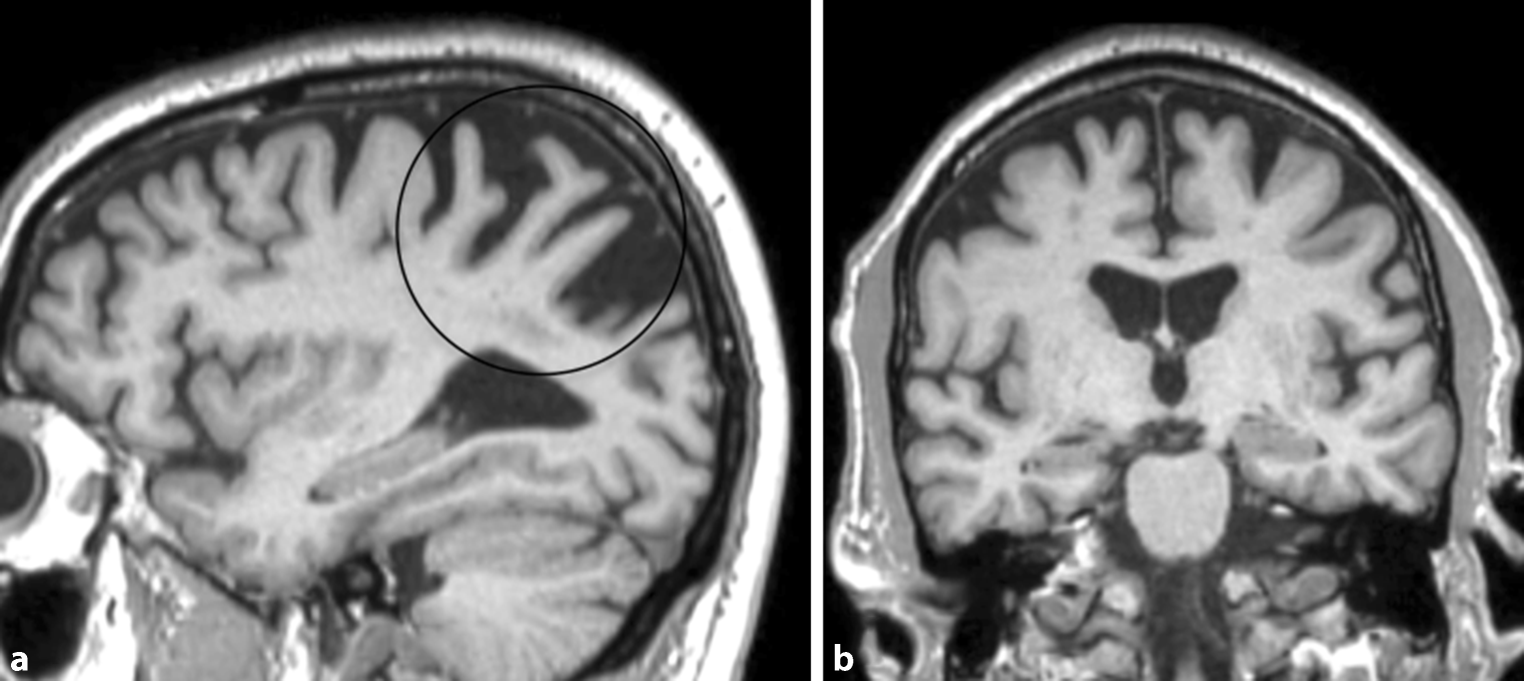

Patients with an atypical Alzheimer’s disease variant, such as early-onset Alzheimer’s disease or a missing APOE E4 genotype show only mild or no hippocampal atrophy, but, instead, present with considerable posterior cortical atrophy, e.g., the precuneus region in early-onset Alzheimer’s disease (illustrated in Fig. 9) [6]. In patients with posterior cortical atrophy, the parieto-occipital and the posterior temporal cortices are most commonly affected asymmetrically, more prominently on the right side, which results in an early visual or visuospatial impairment ahead of cognitive decline [7]. Patients with logopenic progressive aphasia show an asymmetric more prominent left-sided atrophy of the posterior temporal cortex and the inferior parietal lobe, which results in language-related impairments [8].

Fig. 9

Atypical Alzheimer’s disease. A 58-year-old female patient with early-onset Alzheimer’s disease who presented with marked posterior cortical atrophy (depicted in a on sagittal T1-weighted images marked with a circle), while the hippocampi were relatively well preserved (shown in b on coronal T1-weighted images)